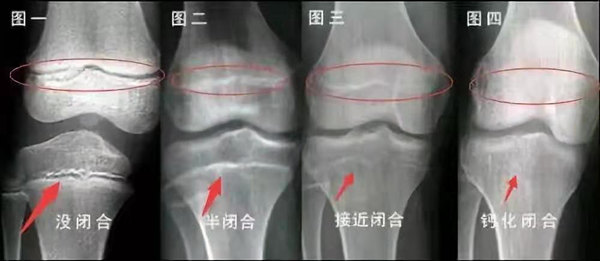

我們都知道,人體的高矮是由骨骼的生長發(fā)育決定的,特別是下肢長骨。長骨呈長管狀,在長骨的兩端有一種專管骨骼生長的骺軟骨,它與干骺端之間有一盤狀軟骨結(jié)構(gòu)稱為骺板(線),在幼兒的X光片上表現(xiàn)為一條較寬的透光帶。 (見下圖)

未成年時隨著年齡的增加骺軟骨端不斷骨化,骨骼就不斷增長。當(dāng)骨骺線完全閉合時骨骼就停止生長,個子也就不再增長了。一般骨骺端完全閉合的年齡是18~20歲左右。

骨骺線提前閉合最多見的情況是性早熟,而這也是很多醫(yī)生專家建議孩子進行骨齡測量的原因之一。另外,在兒童時期大量補鈣也會使骨骺端提前過早閉合。

一般來說,女孩的骨齡超過14歲,男孩的骨齡超過16歲,這時其骨骺線已接近閉合,基本沒有長高的機會了。

因此,越早了解骨骺線閉合情況,越早干預(yù),孩子長高的可能性越大。